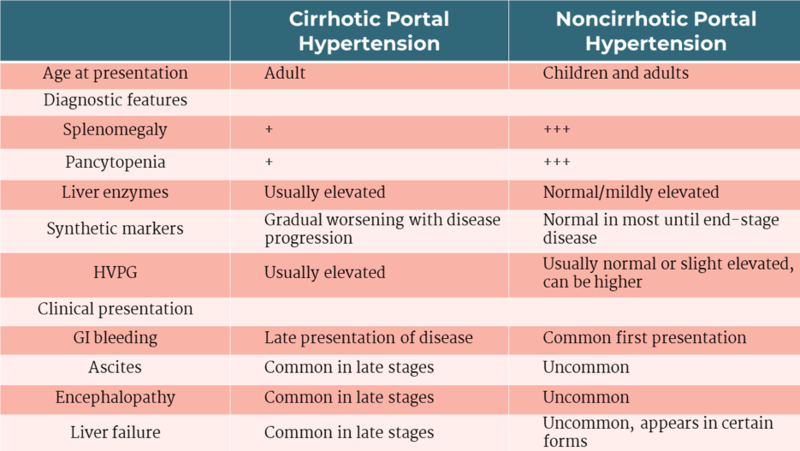

A Puzzling Case Of Portal Hypertension A Collision Between Hema And

A Puzzling Case Of Portal Hypertension A Collision Between Hema And

JCM Free Full Text Portal Vein Thrombosis In The Setting Of

JCM Free Full Text Portal Vein Thrombosis In The Setting Of